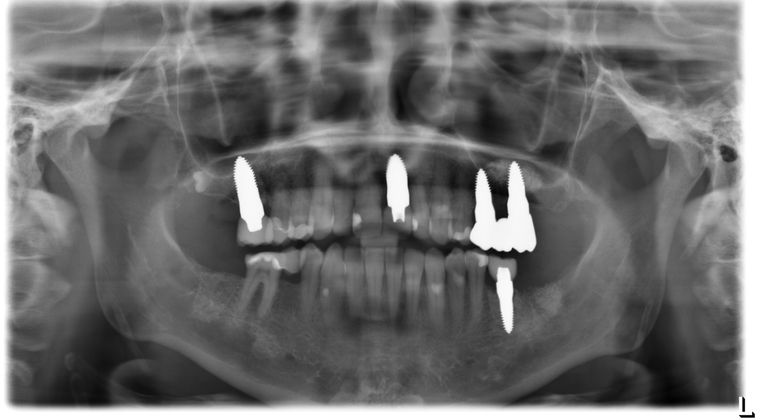

Ein Tätigkeitsschwerpunkt unserer Praxis in Salzburg ist die Implantologie. Wenn ein Zahn fehlt oder entfernt werden muss, sollte immer die Möglichkeit der Implantation im Vordergrund stehen. Ein Implantat verhält sich von den Eigenschaften genau so wie ein natürlicher Zahn. Egal ob nur ein einzelner Zahn vom Zahnarzt ersetzt werden muss oder ein ganzer Kiefer mit festsitzendem Zahnersatz versorgt werden soll, wir finden für Sie eine Möglichkeit, auch wenn die Voraussetzungen ausweglos erscheinen. Wenn möglich versorgen wir unsere Patienten mit Keramikimplantaten. Diese sind immun-neutral und können sehr oft direkt bei der Zahnextraktion eingesetzt werden. Für unsere Patienten ist daher meist nur ein operativer Eingriff notwendig!

- 3D-Röntgentechnik, 3D-Implantatplanung und virtuelle Implantation